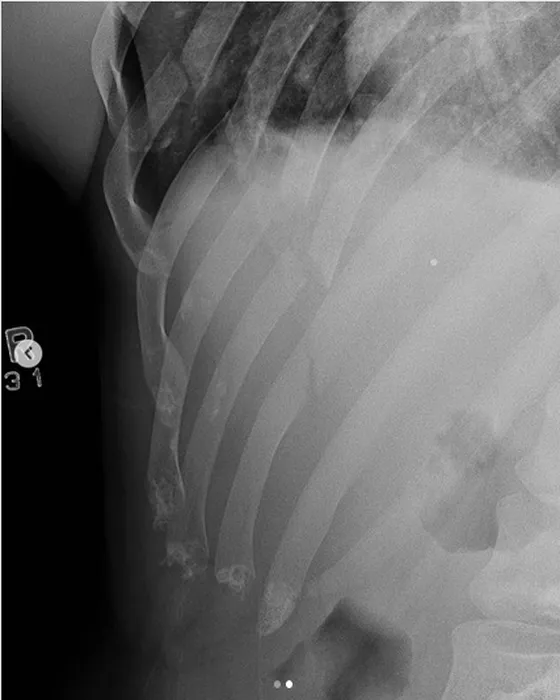

L-a spulberat cu un K.O. horror în meciul de MMA: i-a rupt dintr-un picior 5 coaste și i-a perforat plămânul! Victima a fost operată de urgență | VIDEO